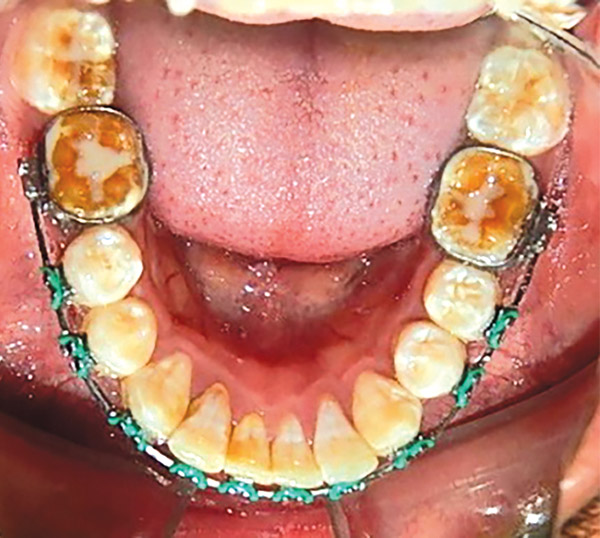

En las fotografías intraorales se muestra la fluorosis dental Tf4 y Tf7, las relaciones molares clase II molar y canina bilateral (Figura 3 y 4), el apiñamiento severo superior e inferior, con el órgano dental 35 en infraoclusión. El overbite aumentado y las líneas medias dentales no son coincidentes (Figura 5), las formas de arco superior e inferior son cuadradas (Figura 6 y 7).

Figura 7. Inferior.